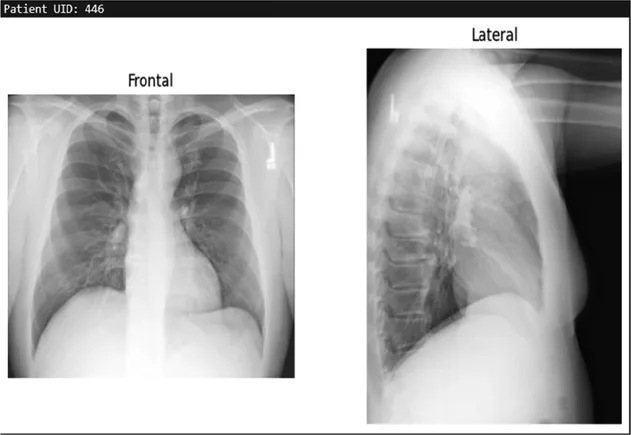

Training details

The dataset used in this study is the Indiana University Chest x-ray Dataset, which consists of 7,430 images of frontal and lateral chest x-rays belonging to 3,825 patients. Each image is paired with corresponding radiology reports that provide detailed findings regarding the patients' conditions. This dataset serves as the foundation for training the model to generate textual descriptions based on visual inputs.

Table 3. Example predictions of ChestX-transcribe.